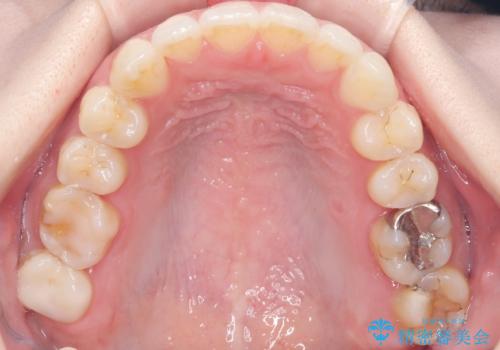

- 治療計画

今回のワイヤー矯正治療では、抜歯せずに歯を並べるスペースを作るため、特殊な小さなインプラントであるアンカースクリュー(TAD)を一時的に使用しました。このアンカースクリューを固定源として、奥歯(臼歯部)全体を後方へ遠心移動させました。従来の矯正では難しかったこの奥歯の移動を確実に行うことで、前歯の八重歯を適切な位置に並べるスペースを確保。治療の結果、抜歯することなく右上の八重歯と叢生が解消され、機能的にも審美的にも整った美しい歯並びを獲得していただけました。